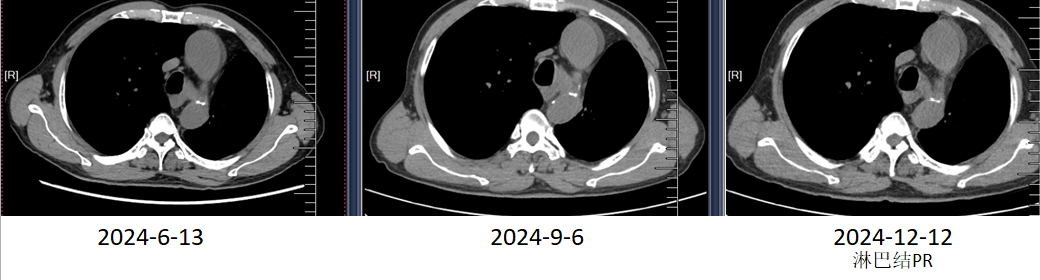

2024-6-13,复查胸部CT可见纵膈淋巴结较前增大(大者短径原7mm,现11mm)。

2024年9月,复查胸部CT可见纵膈淋巴结较前增大,并出现融合(大者短径16 mm)

疗效评估:PD。

2024-12-12,复查胸部CT可见,纵膈淋巴结较前稍缩小(大者短径11mm)。

疗效评估:淋巴结PR,肺部未见新发病灶。